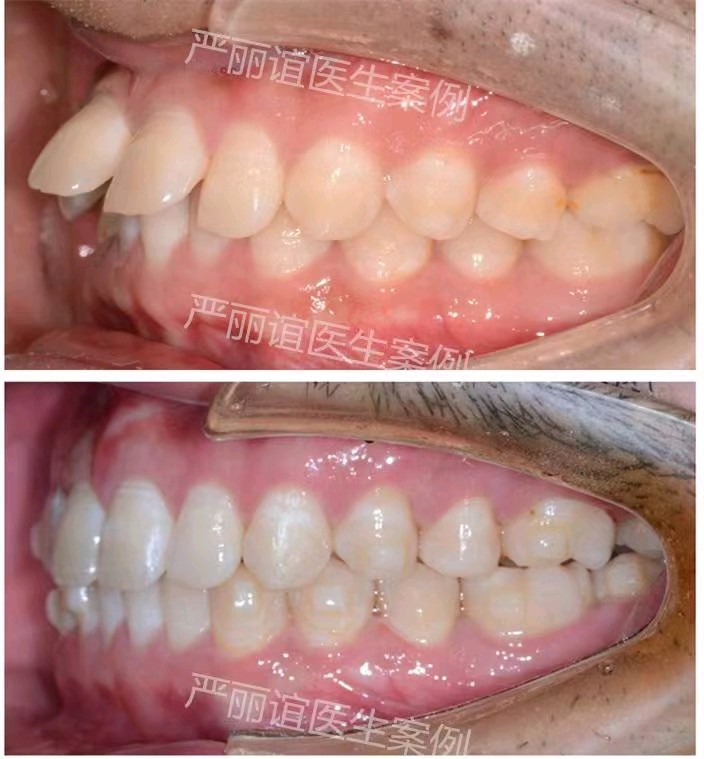

患者:成年男性

主诉:微笑时门牙有缝影响美观,要求矫正。

结果:牙性前突    深覆合II    深覆盖II

矫正方案:不拔牙矫正,下颌前牙少量片切,排齐整平上下颌牙齿,压低下颌前牙,内收上颌前牙,关闭上颌牙缝。

矫正时间:1.5年。